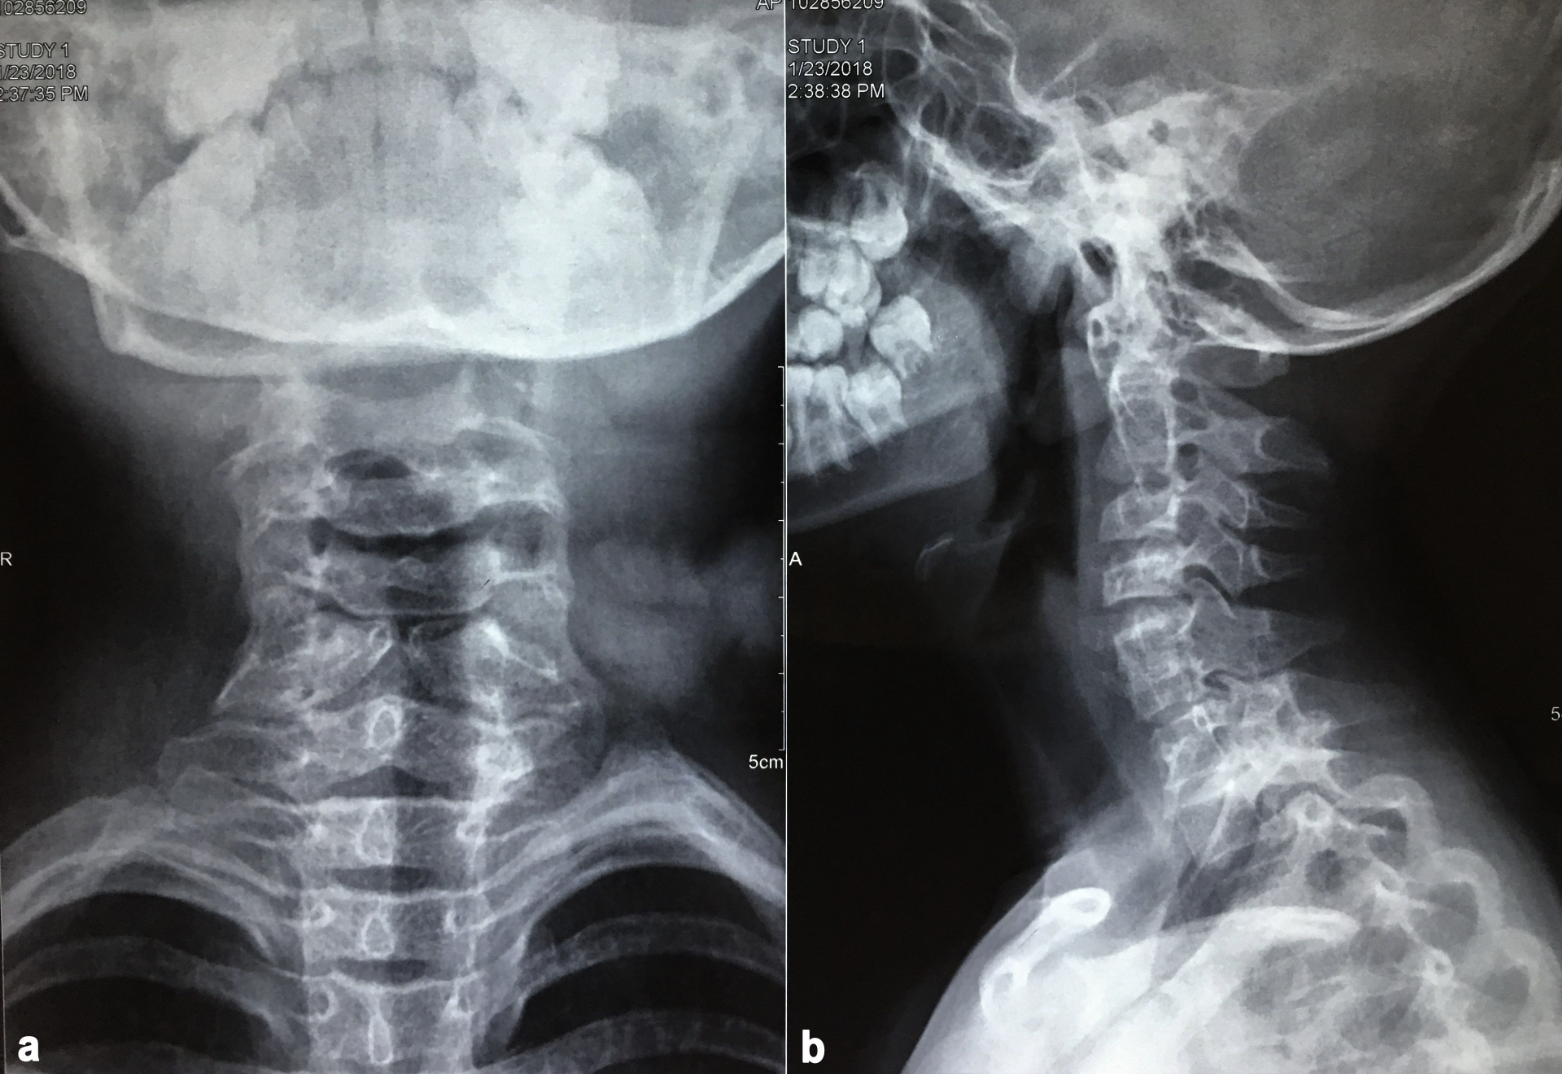

During work-up for surgery, chest radiographs revealed dextrocardia that was further confirmed on a 2D echocardiography (Figure 2). A cervical radiograph revealed the presence of hemivertebrae and butterfly vertebrae at C4 to C6 (Figure 3). Ultrasonography of the abdomen revealed situs inversus. No gastrointestinal or urogenital tract anomalies were detected. Cross-sectional imaging was not performed because the patient was asymptomatic, and echocardiography was normal. A template was constructed based on the opposite ear to guide cartilage carving intraoperatively (Figure 4).

Besides cardiac implications, our patient also had cervical vertebral anomalies. Both hemivertebrae and butterfly vertebrae are typically found in thoracic and lumbar regions and are rare in the cervical spine. However, their presence necessitates a comprehensive airway examination because neck mobility may be restricted due to pain or abnormal curvature and may cause a difficult intubation.8,9